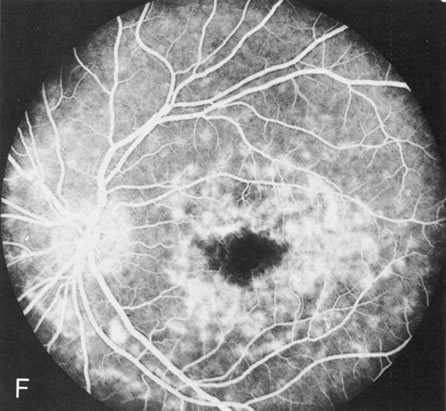

Dye leakage in RP may occur from the retinal vessels or at the level of the retinal pigment epithelium (Fig. 1B).2–4 The leakage may be seen in the macula and posterior pole, along the vascular arcades in the distribution of the radial peripapillary capillaries, and in the periphery (where an exudative vasculopathy resembling Coats' disease is suggested).

Of more clinical importance is the role of FA in the diagnosis and treatment of cystoid macular edema (CME) (Fig. 1C and D). Stereoscopic FA indicates that the leakage, which may be diffuse or have the typical petaloid stellate appearance of CME, can come from the perifoveal retinal capillaries, from the choroid through the RPE, or from a combination of both sources.4 With the recent suggestion that CME in RP may be successfully treated with acetazolamide,5, 6 FA is thus important to document the diagnosis of CME, establish the origin(s) of leakage, and follow patients during and after therapy.